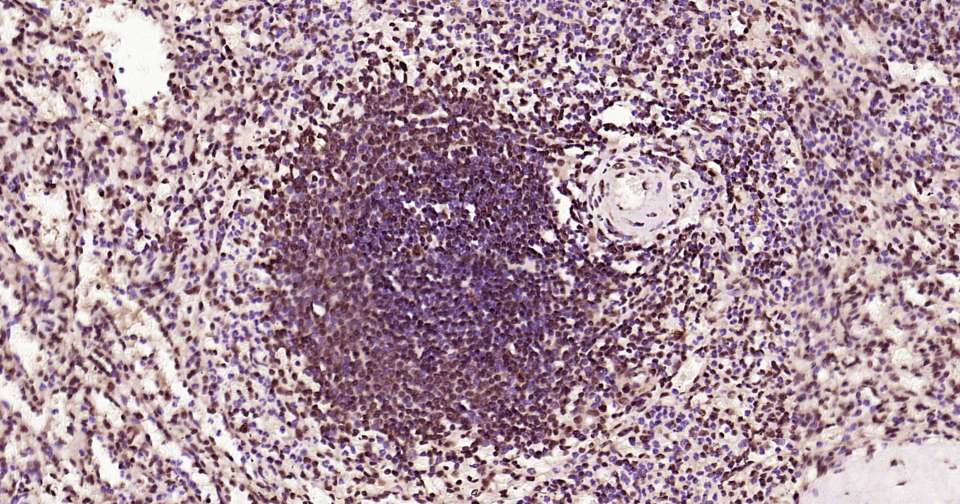

Immunohistochemical analysis of paraffin embedded human spleen tissue slide using IHC0368H (Human HES5 Kit).